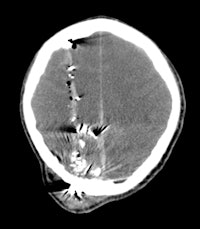

Plain radiography and CT are the most commonly used modalities for imaging of gunshot wounds, but angiography and MRI are playing an increasing role, according to research presented at the 2011 U.K. Radiological Congress (UKRC) in Manchester.

Doctors involved in the care of these patients need to understand the patterns and mechanisms of the injuries, he explained. To accurately interpret images of gunshot wounds, a basic knowledge of ballistics is important, especially the factors affecting the extent and type of tissue damage. Such knowledge is useful not only for evaluating acute injuries but also for determining the path of the missile, awareness of missile fragmentation, and embolization, thus contributing to the overall clinical, and often the forensic, picture.

The two mechanisms of tissue injury that account for the majority of damage caused by a bullet are direct crushing of tissue by the projectile (causing a permanent cavity) and temporary cavitation, which stretches and tears surrounding tissues. Increased velocity, fragmentation, deformation, and rolling/spinning of the bullet will cause more damage by both these mechanisms, he pointed out.